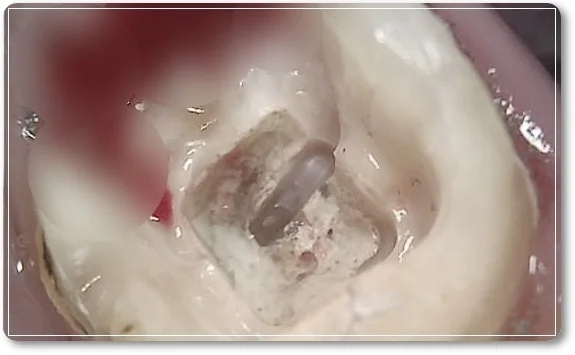

크라운을 제거한 뒤 내부에 있던 금속 기둥을 제거하기 시작했지만 예상했던 것처럼 쉽지 않은 과정이었습니다.

시간을 들여 제거 작업을 진행하던 중, 금속 기둥 아래쪽에서 균열이 있는 부분을 확인할 수 있었습니다.

치아가 더 손상되거나 갈라지지 않도록 주의하면서 조심스럽게 금속 기둥을 제거하는 과정을 마무리했습니다.

금속 기둥을 제거한 뒤 기존에 신경치료가 되어 있던 부위가 드러났습니다. 이후 내부에 채워져 있던 신경치료 재료를 모두 제거하고, 재신경치료 과정을 진행하게 되었습니다.